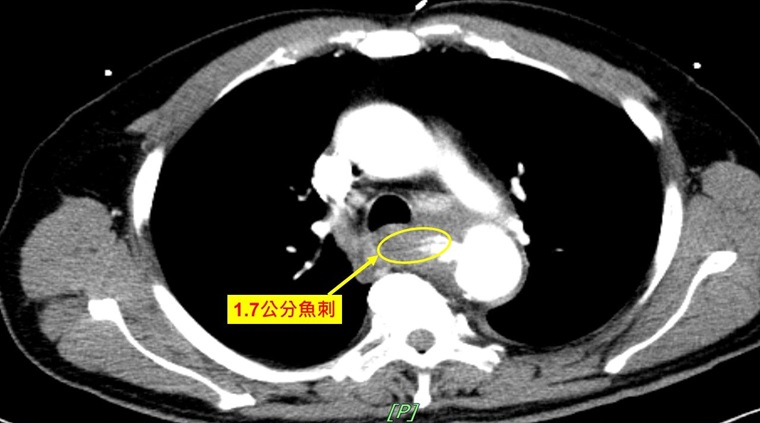

▲誤食1.7公分魚刺竟造成腸胃道穿孔,甚至導致主動脈食道廔管,而危及生命。(圖/奇美醫院提供)

【NOW健康 連慧婷/台南報導】72歲男士阿財(化名),去(111)年9月時,因發燒、背痛、右上腹痛由救護車送至奇美醫院急診就醫,抵達急診室時,血壓只有81/65mmHg(正常值為120/80mmHg)。阿財告知醫師,1個月前吃吳郭魚時,有誤吞魚刺,但因身體無礙並未就醫,結果急診醫師經影像學檢查發現,患者疑似主動脈瘤破裂,立即通知心臟血管外科主治醫師吳依璇協助處置,經診斷後,醫師研判是因長達1.7公分的魚刺穿破食道與主動脈,而導致主動脈食道廔管,並造成腸胃道穿孔、大量出血,因此緊急執行主動脈內覆膜支架置放手術,穩定生命跡象。